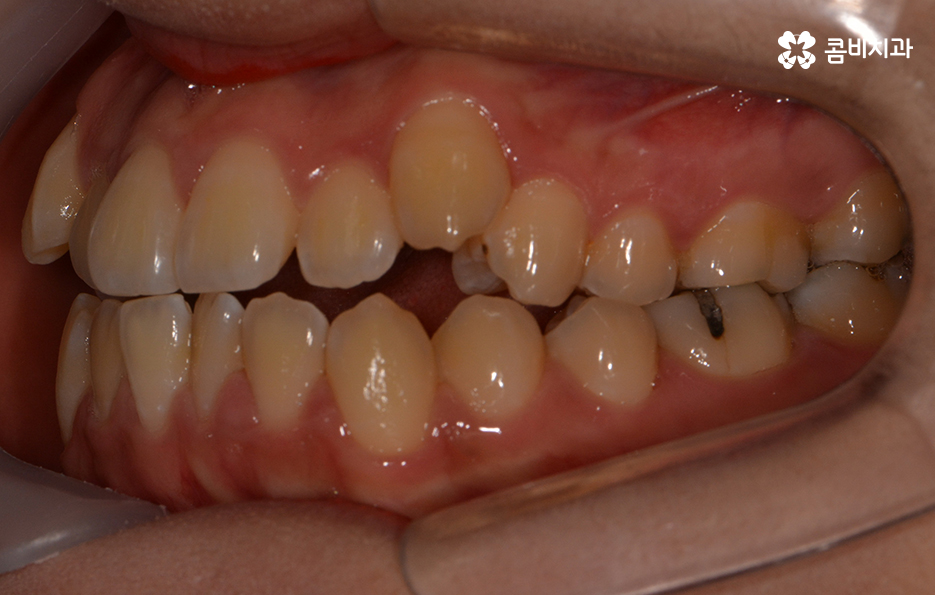

위 환자분의 경우에는 비발치로 송곳니 덧니 교정이

진행된 사례이며 전체 진료 기간은 약 1년 6개월가량이 소요되었습니다.

송곳니 덧니 치료를 할 때 주의해야 할 점은

자신의 골격과 얼굴형을 충분히 생각해야 한다는 것입니다.

계실 수 있겠지만 치아가 돌출되어 있으신 경우에는

옆모습이 돌출입으로 보일 수 있기 때문에

앞모습과 옆모습, 전체 얼굴형을 고려하여

자신의 얼굴과 자연스럽게 어울리는 결과가 중요합니다.